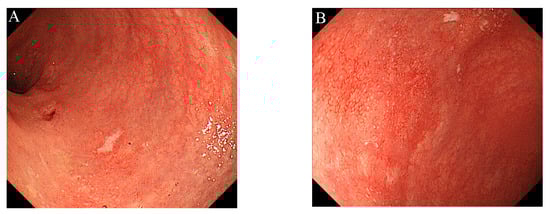

To maintain the remission, 20 mg/day of TOF was continued. His general condition improved, and discharge was considered. Suddenly, on the 29th day of hospitalization, he developed fever and chest pain. Serum C-reactive protein level was markedly increased. Suddenly, he developed fever and chest pain on Day 29. Serum C-reactive protein level was markedly increased. Computed tomography (CT) of the chest showed an emphysematous bulla in the upper left lobe of the lung and fluid formation inside the bulla (Figure 2). He was diagnosed with lung abscess by a pulmonologist and was started on meropenem. Table 2 shows the patient’s laboratory data at the onset of lung abscess. TOF was discontinued. The treatment was successful, and the imaging findings improved. He resumed TOF on Day 37 of his hospital stay and was discharged on Day 42. At present, his remission is maintained with continued with TOF alone, and he has not experienced any adverse event, including a relapse of the lung abscess. The patient’s clinical course is shown in Figure 3. One year after being treated with TOF alone, the endoscopic findings of mucosal inflammation had improved (Figure 4 A,B).

Figure 4. Colonoscopy showed mild inflammation in the colorectal mucosa, after one year of treatment with tofacitinib alone: (A) Sigmoid colon; (B) Rectum.